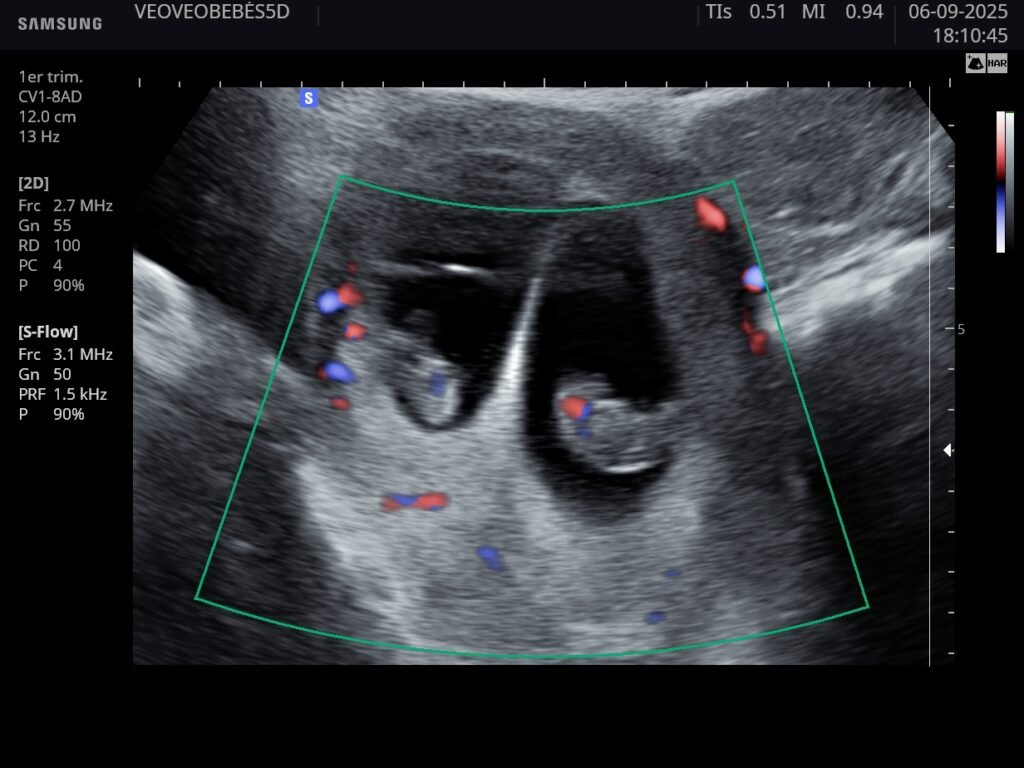

Sí, son completamente seguras. Utilizamos equipos de ultima generación que emite una cantidad mínima de energía, lo que permite obtener imágenes de alta calidad sin riesgo para el bebe ni la madre.

La ecografía 3D muestra imágenes estáticas, la 5D añade movimiento en tiempo real con mayor nitidez, y la foto HIPERREALISTA ofrece una calidad mas clara de la cara del bebe y con detalles únicos.

La ecografía medica se centra en el control clínico de embarazo, mientras que la ecografía emocional 5D busca disfrutar del momento y conocer la carita del bebé con imágenes únicas.